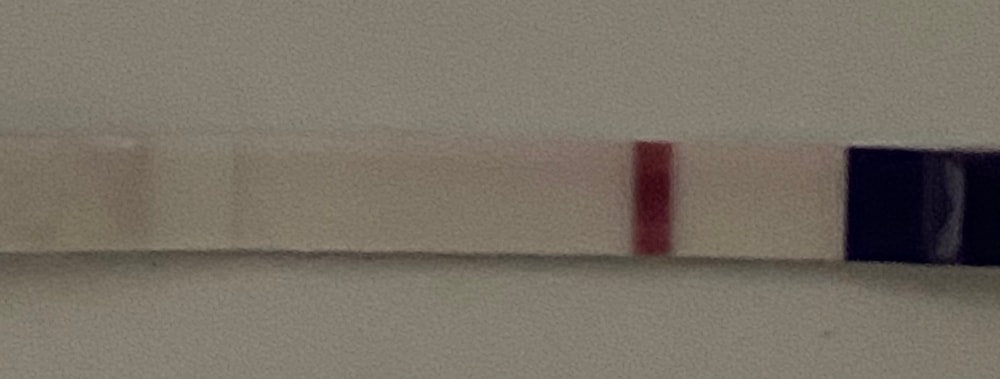

Вчера клиаблю непонятно что мне нарисовал, поэтому сегодня я снова сделала тест))

фоткала под разными освещениями. Очень уж хочется, чтобы кто-то кроме меня тоже увидел полоску🤣🤣 фотки, где теста два - верхний это вчерашний утренний, а нижний сегодняшний. Видите ли вы что-нибудь?🥺

На нижнем вижу //

Я вижу, цепляет глаз. У меня 7-8 дпо, сама начала тесты делать, хотя понимаю рано. Но разглядываю и надеюсь